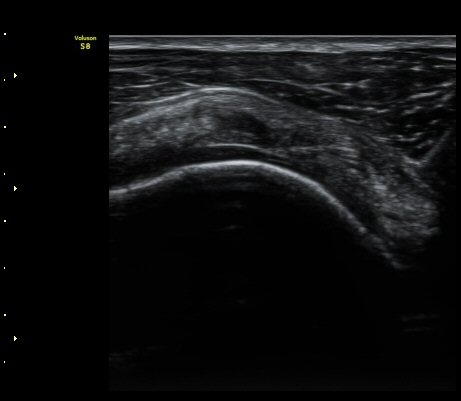

À̵Π¹Ú±Ù°Ç Ⱦ´Ü¸é°Ë»ç¿¡¼­ ƯÀÌ ¼Ò°ßÀ» º¸ÀÌÁö ¾ÊÀ½(»çÁø 1)